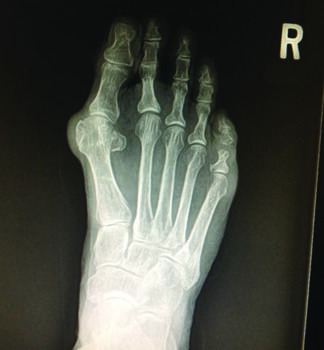

One may choose to begin with standard radiographs for workup of plantar plate injuries. Although the plantar plate is not visible on plain X-ray, the structure of the foot and parabola of the metatarsals can provide useful information, in my opinion. The level of hammertoe deformity, medial or lateral shift of the toe at the MPJ, metatarsal length, and bunion deformity are all potential metrics to consider. Magnetic resonance imaging (MRI) is the mainstay of diagnostic tools in plantar plate analysis. In acute injuries, MRI will often reveal acute tears with associated fluid. In chronic injuries, fibrous scar formation can exist in addition to a tear.6 Checking for a neuroma on MRI is also a consideration when possible.